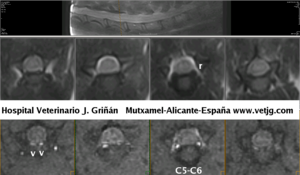

Resonancia magnética de perro cocker, a nivel de columna cervicotorácica (C5-C6) donde se muestran los senos venosos (v), hiperintensos en STIR e hipointensos en SE T2w, que circulan juntos a nivel de la mitad del segmento medular, y se separan a nivel radicular (r), describiendo un trayecto serpenteante por el suelo del canal raquídeo. Los núcleos pulposos se encuentran degenerados (relativamente poco intensos en T2w)